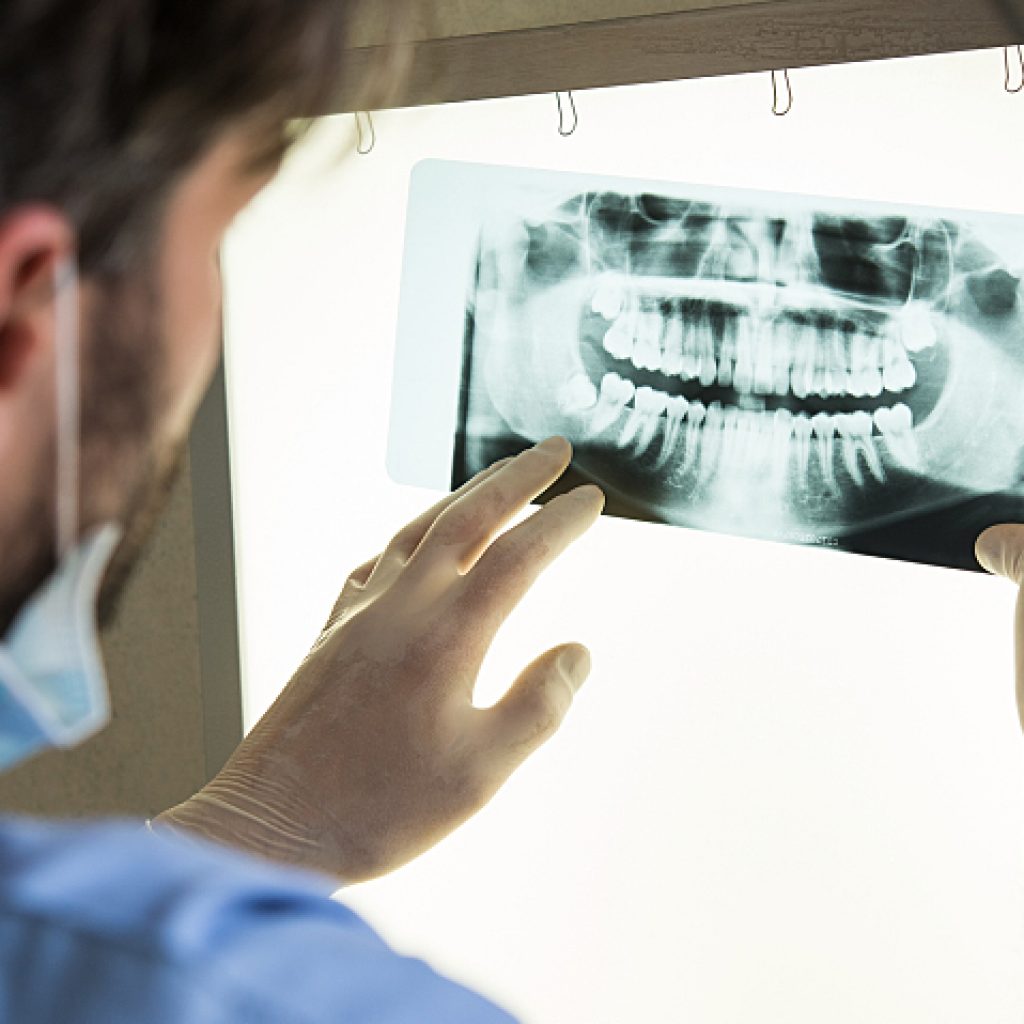

Keep an eye on bone loss-

When you have a missing tooth, one of the main issues that come across is bone loss. Greater bone loss may disqualify you as a dental implant candidate. A dental X-ray provides insight into the situation.

To summarise, discuss your health conditions and get a dental X-ray done. The dentist then makes an informed decision about the suitability of dental implants for the patient.